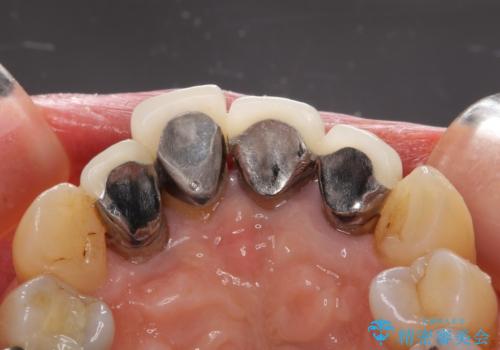

クラウン治療は経年的に歯ぐきの位置が変わり汚れが溜まってしまったり、見た目が悪くなるなどの問題が出てくることがあります。

現在の歯ぐきの位置できっちりと仕上げることで見た目の改善が達成されました。